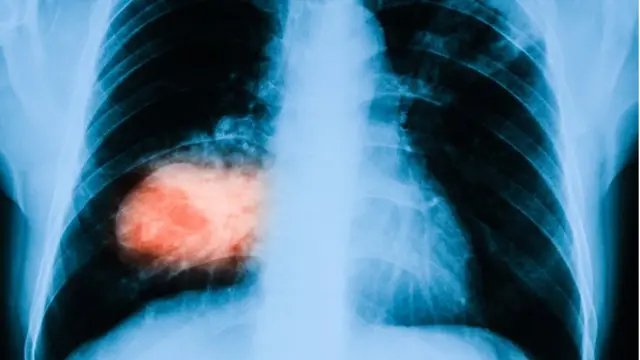

خو د دغو کلينيکي نښو په شتون کې د زړه ګراف(اي سي جي) کې ځينې بدلونونه، د سينې نارمل اېکسرې، په وينه کې د (ډي ډایمر) لوړه کچه او د سږیو نه په را غبرګه شوې (شریاني) وینه کې د آکسیجن ټيټه کچه یې شک پیاوړی کوي او پلمونري انجیوګرافي(سي ټي پي اې) یې تشخيص کره کوي.

د عکس سرچینه، Getty Images

که د غوټې یا کلاټ سایز وړوکی وي نو ښایي هېڅ یا لږ دغه ډول نښې نښانې وموندل شي خو یوه یا څوغټې غوټې یا (کلاټس) د سږیو د لوی رګ یا رګونو د بندېدو او د بنیادم د چپه کېدو(کولپس) او ناڅاپي مرګ سبب هم کيږي.

د (ډي وي ټي) په څېر د (پي اي) درملنه هم د بېلابېلو انټي کاګولېنټ درملو په ذريعه کيږي چې له څو میاشتو نيولي په ځينو کسانو کې ترټول عمره دوام کوي.